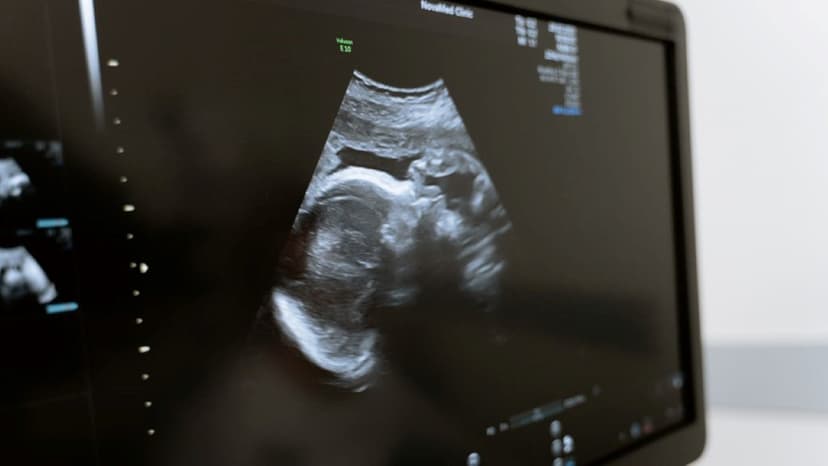

Mang thai ở tuổi 40 mang lại nhiều niềm hạnh phúc nhưng cũng đi kèm không ít thách thức về sức khỏe cho cả mẹ và bé. Ở độ tuổi này, các biến chứng thai kỳ như tiểu đường thai kỳ, tăng huyết áp hay dị tật nhiễm sắc thể có xu hướng tăng cao. Vậy phụ nữ 40 tuổi mang thai cần bổ sung gì để đảm bảo một thai kỳ an toàn? Hãy cùng Thu Cúc TCI tìm hiểu chi tiết các dưỡng chất thiết yếu qua bài viết dưới đây.

Trước khi đi sâu vào vấn đề dinh dưỡng, nhiều người thường thắc mắc phụ nữ 40 tuổi có dễ mang thai không. Thực tế, khả năng sinh sản của phụ nữ giảm dần theo tuổi tác, đặc biệt là sau 35 tuổi. Tuy nhiên, với sự phát triển của y học hiện đại, có nhiều phụ nữ mang thai tuổi 40 vẫn có thể sinh con hoàn toàn khỏe mạnh nếu được chăm sóc và bổ sung dinh dưỡng đúng cách.